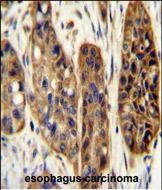

分类: 科研抗体货号: P30896别名: Zinc finger CCCH domain-containing protein 3, ZC3H3, KIAA0150, ZC3HDC3应用: WB,IHC反应种属: Human